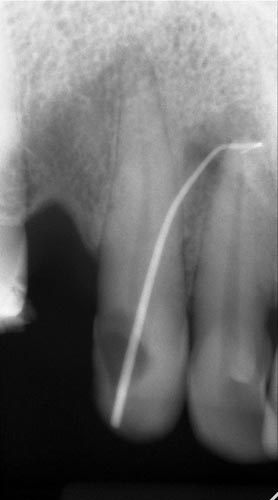

Зонування ПДЛ, холодовий тест, порівняльна перкусія, пальпація, дрілл тест, вибіркова анестезія, трейсинг, порівняння інформативності КТ та інтраорального тесту, правильні укладання для проведення якісних рентгенографічних досліджень, як своїми руками зробити позиціонер для інтерпроксимального знімка. Складні клінічні кейси, які потребують клінічного досвіду.